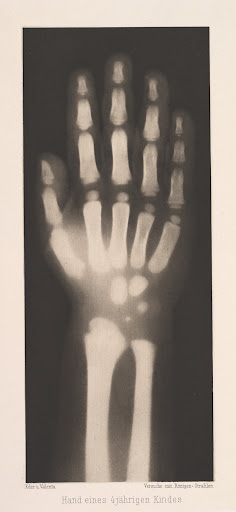

| 德國物理學家亨特根(Wilhelm Conrad Röntgen)1895年 在〈關於一種新的射線〉(Über eine neue Art von Strahlen)中所發表的圖像。 |

1895年11月8日,德國物理學家亨特根(Wilhelm Conrad Röntgen) 正埋首研究光和電磁波的相似性。當他在黑暗中看到在螢光屏幕上閃爍的燐光時,或許他壓根沒有想到,他會因為這一次「意外」,發現了後來的「X光」。(註一)亨特根當時使用的實驗設備再尋常不過,幾乎每個實驗室都擁有相同的器具。在亨特根之前,更有許多的科學家曾經用相同的實驗來觀察電磁波。甚至也已經有人發現,當攝影底片會因為靠近陰極射線管而曝光。不過亨特根和其他科學家的不同之處在於,他第一次正視那個過去被視為「誤差」、「錯誤」的現象,第一次系統性地去實驗X光的穿透性和在相紙上顯影的能力,確定了「X射線」的存在。同年12月28日,他在〈關於一種新的射線〉(Über eine neue Art von Strahlen)中發表了他的發現,轟動了歐美科學界,後來更在1901年獲頒第一屆諾貝爾物理學獎。而他當初在文章裡所公開、他妻子左手的相片更成為了歷史上最有名的一張X光片。

以上圖片出自Josef Maria Eder《Versuche über Photographie mittelst der Röntgen'schen Strahlen》,1896年。